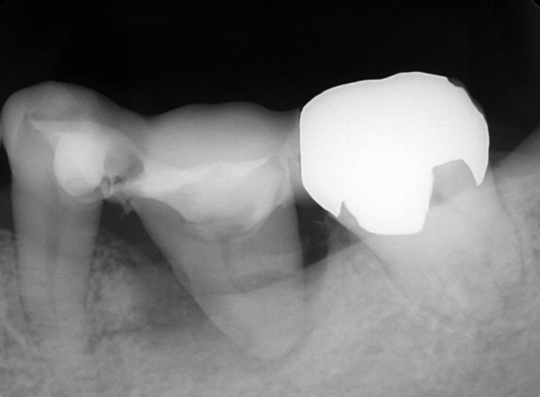

術後

移植直後は支える骨が少ないです。